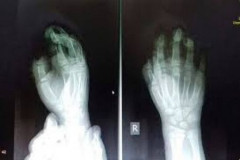

Պայթուցիկից տուժած երեխայի երկու մատը վերականգնվել է. «Սուրբ Աստվածամայր» ԲԿ-ի տ...